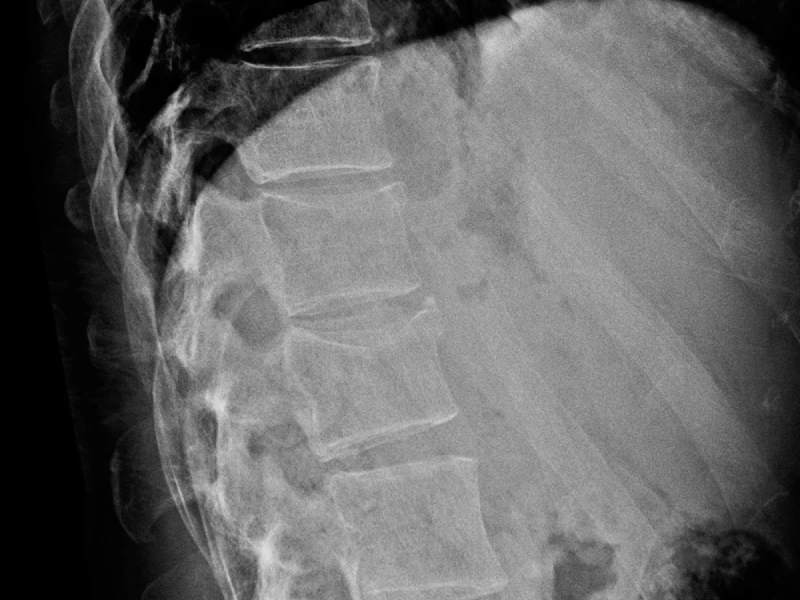

Fractura vertebral en la unión toracolumbar (D12–L1) Presentación Edad: N/A Género: Femenino Radiografías AP y lateral de columna lumbar, incluye